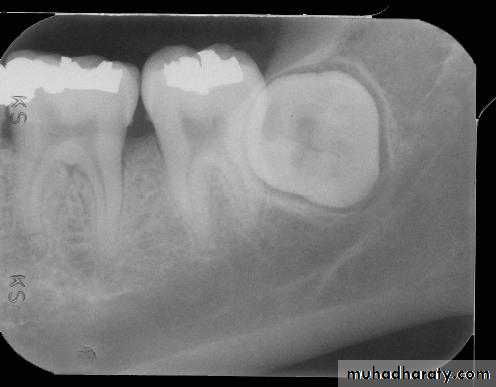

Teeth are composed of pulp (arrow on the secondmolar), enamel (arrow on the first molar), dentin (arrow onthe second premolar), and cementum (usually not visibleradiographically).